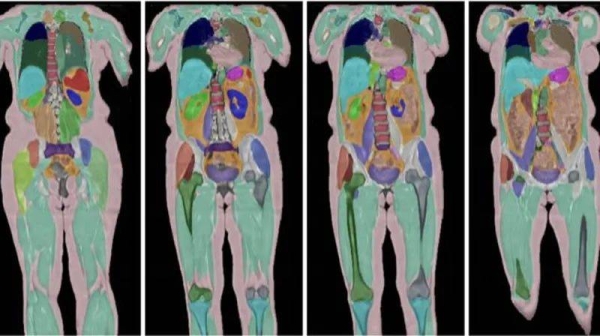

لندن – يقول العلماء إنه يمكنهم دراسة أجسادنا مع تقدمنا في العمر بمزيد من التفاصيل من أي وقت مضى ، وذلك بفضل أكثر من مليار عملية مسح للمتطوعين في المملكة المتحدة.

يقول أكبر مشروع للتصوير البشري في العالم إنه حقق الآن هدفه المتمثل في مسح الأدمغة والقلوب وغيرها من الأعضاء التي تبلغ 100000 شخص – تتويجا لدراسة طموحة لمدة 11 عامًا.

شاهدت بي بي سي عندما دخل ماسحة التصوير بالرنين المغناطيسي الكامل للجسم في حديقة صناعية خارج القراءة ، وظهرت صور مفصلة لخلايا الدماغ والأوعية الدموية والعظام والمفاصل على الشاشات.

يتم منح المشاركين موعدًا مدته خمس ساعات للمسح الضوئي باستخدام خمسة أنواع مختلفة من الآلات التصوير بالرنين المغناطيسي والأشعة السينية والموجات فوق الصوتية.

بدأ جزء التصوير من المشروع في عام 2014 ، ويتضمن إجراء عمليات مسح مفصلة من 100000 من هؤلاء المشاركين أنفسهم.

من خلال الجمع بين تلك الفحص مع البيانات الأخرى التي جمعتها البنك الحيوي في المملكة المتحدة ، يمكن للعلماء اختبار ما إذا كانت التغييرات المبكرة في تكوين الدماغ أو الجسم تؤدي إلى أمراض أو مشاكل صحية أخرى في الحياة اللاحقة.

“لتحليل هذه الصور يدويًا كان من شأنه أن يستغرقنا آلاف السنين ولكن الآن … يمكننا استخراج جميع المعلومات تلقائيًا ، حتى نتمكن من قياس كل شيء في الجسم في غضون دقائق.”

يستخدم الباحثون بشكل متزايد الذكاء الاصطناعي (AI) لمعالجة الكميات الضخمة من البيانات الناتجة عن المشروع.